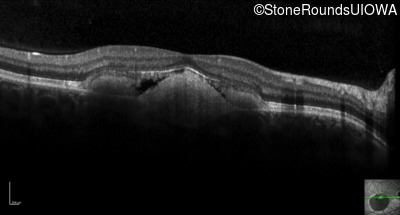

Visit at age: 16 years

Optical Coherence Tomography - Right - 20/40 +2 sc

Exemplar / OCT Stack